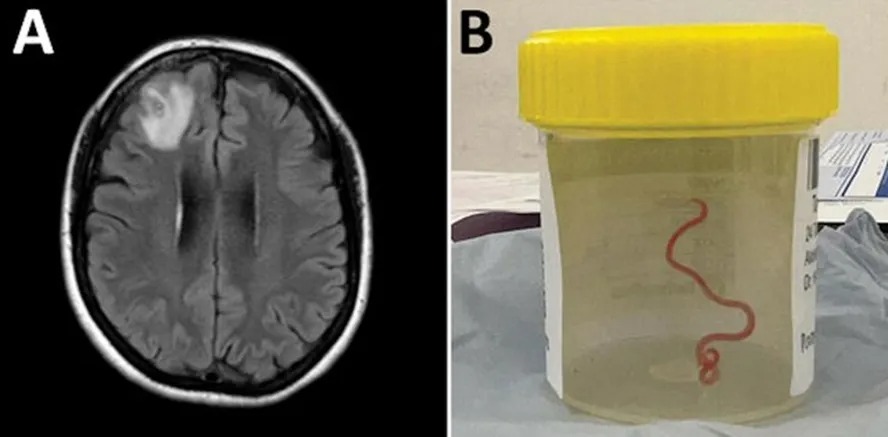

Tomografia e ressonância mostraram dezenas de lesões no encéfalo — estruturas arredondadas cheias de líquido típicas de cistos. A investigação apontou o culpado: neurocisticercose, infecção causada pelas larvas da tênia Taenia solium, o “verme do porco”.

O paciente precisou de internação e recebeu antiparasitários combinados a anti-inflamatórios para conter a inflamação cerebral. Segundo os relatos do caso, o quadro evoluiu com melhora após o tratamento.